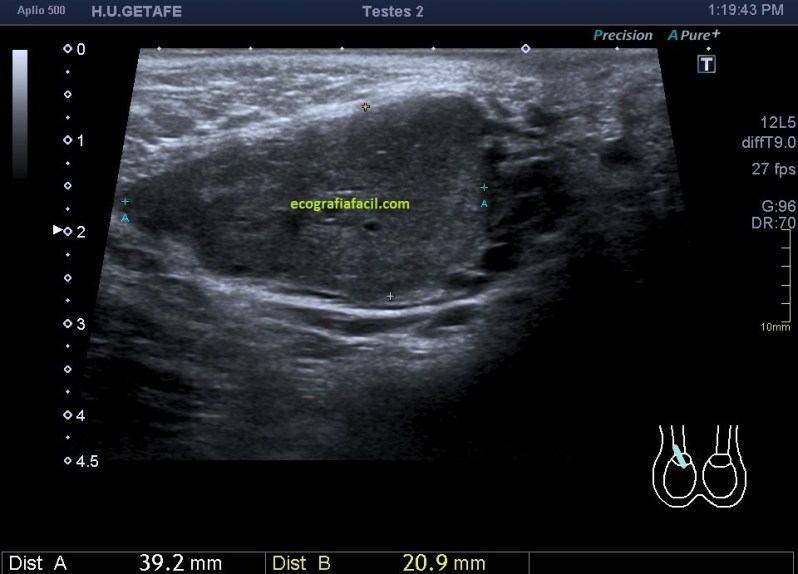

En cuanto la paciente me indicó su zona de dolor y pude el transductor observé una imagen mal definida que ocupaba la porción inferior del músculo recto abdominal derecho (coincidiendo con foco doloroso), se visualiza una lesión de ecogenicidad heterogénea (predominio hipoecogénico) con bordes irregulares de aproximadamente 2,5 cms en su eje más largo.

Una vez que tuve controlado el aspecto normal de músculo en la misma localización donde la paciente tenía el bulto, me dirigí a la región del bultoma y estudié la lesión, descrita con anterioridad, siguiendo el protocolo de actuación en caso de neoformaciones, control, medidas, doppler color y power y finalmente comparativa.

Semiológicamente es evidente una desestructura en el vientre muscular de recto anterior, que borra el aspecto normal del músculo y lo aumenta de tamaño aumentado su hipoecogenicidad. Los bordes son irregulares y de márgenes mal definidos.